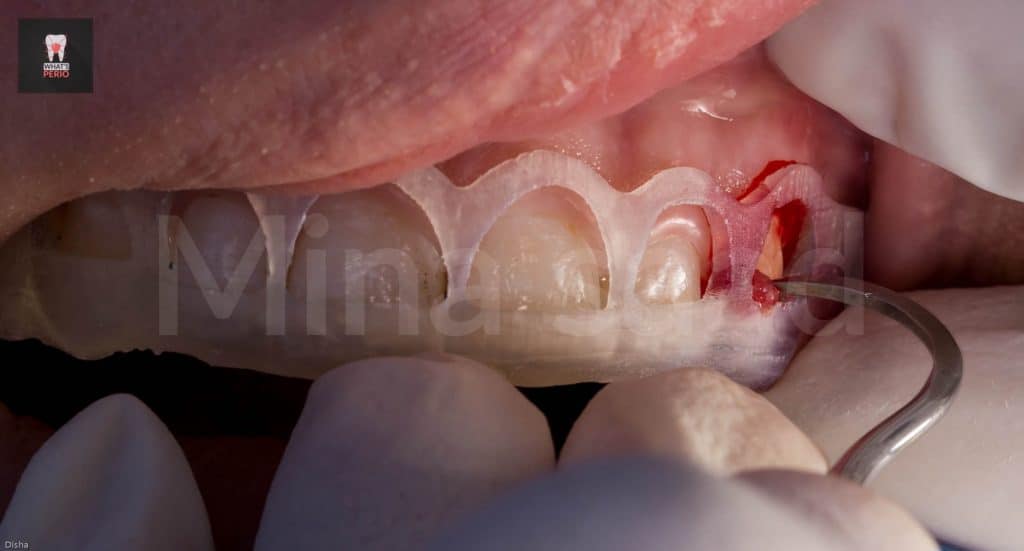

-The guide was printed & was tried over a 3d model & also intraorally to check the coronal level is exactly like the pobing depths which were taken.

-External bevel gingivectomy was made while the guide in place.

-The guide was placed again over labial plate of bone & it was noted that its apical level is higher than alveolar crest level.” Which confirms that the design on CBCT was accurate”

-A periodontal probe was placed between CEJ & alveolar crest to measure the distance which was 2mm. “ensuring that the digital guide is accurate”